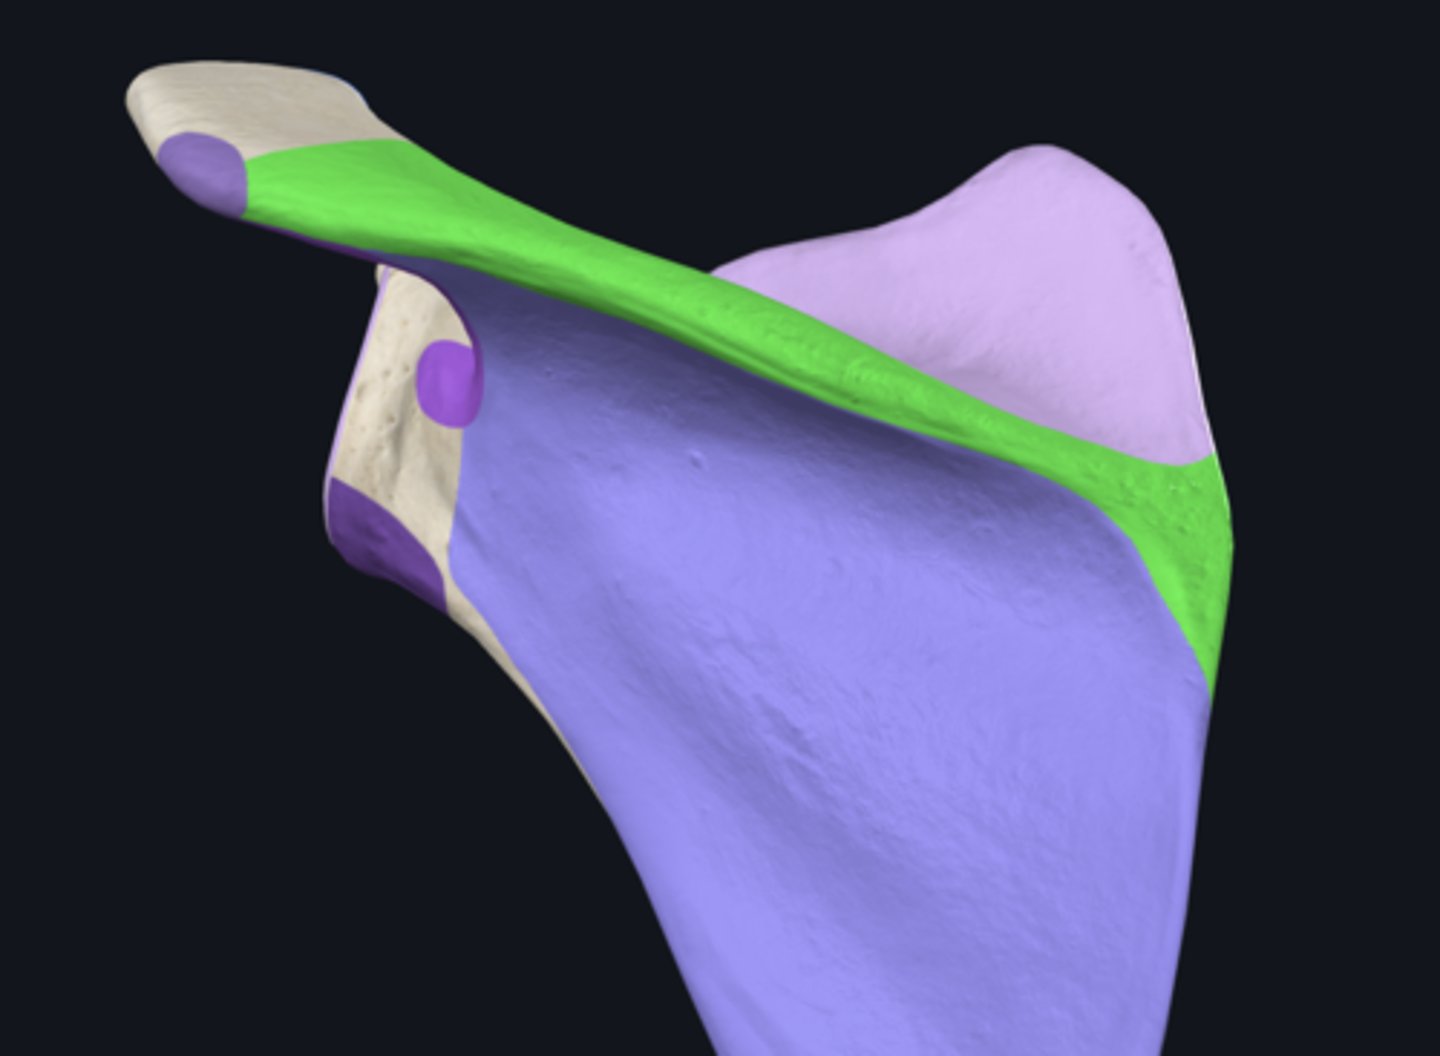

Acromion

Superior angle of scapula

Coracoid process

lateral border of scapula

medial border of scapula

inferior angle of scapula

body of scapula

posterior surface of scapula

superior border of scapula

acromial angle

infraspinous fossa

spine of scapula

subscapular fossa

supraspinous fossa